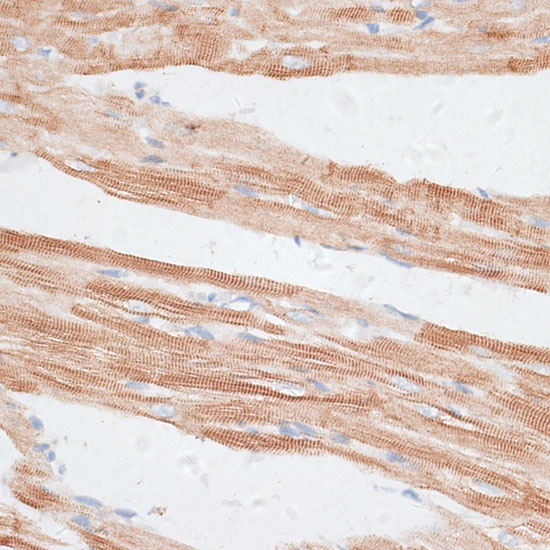

Immunohistochemistry of paraffin-embedded rat heart using GRK5 at dilution of 1:100 (40x lens).

Immunohistochemistry of paraffin-embedded mouse heart using GRK5 at dilution of 1:100 (40x lens).